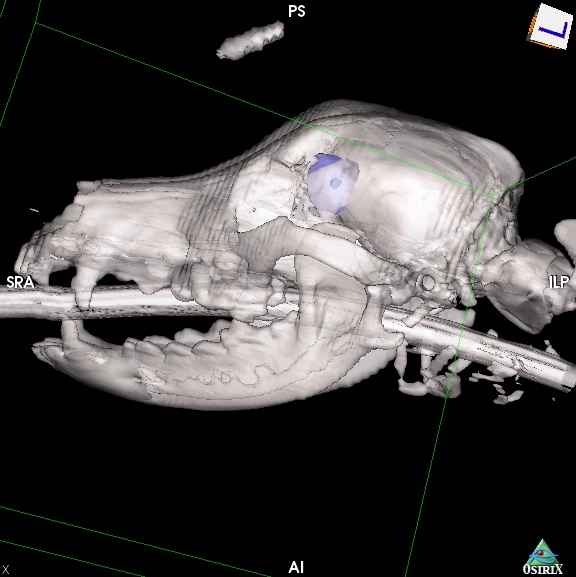

犬の脳腫瘍(髄膜腫)について

髄膜腫は脳の外側、頭蓋骨の裏側にある硬膜という膜から発生する腫瘍。つまり脳そのものから生じる腫瘍ではなく、脳の外側から発生して脳を外側から圧迫する。